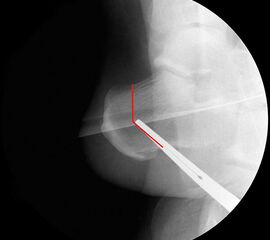

Durch eine V-förmige Schnittführung kann eine Translation des Tuber calcanei nach dorsal zuverlässig verhindert werden, bei hoher primärer Stabilität.

Operationsplanung anhand der Röntgenaufnahmen unter Beachtung wichtiger radiologischer Landmarks wie Rückfussachse, Metatarsale I – Talushals-Achse im dp und lateralen Strahlengang (Abbildung 1 und 2).